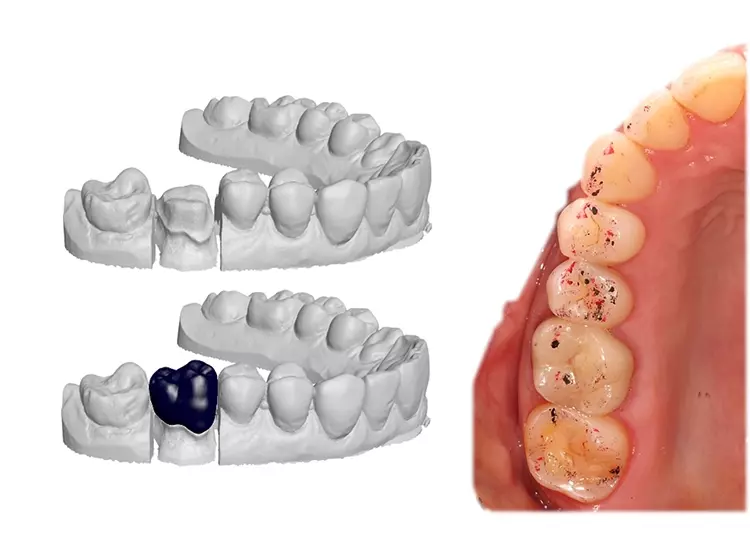

Ihr Videofilm dokumentiert die Rehabilitation des frakturierten Frontzahns 12 sowie der verloren gegangenen Vertikaldimension aufgrund erosiven Zahnhartsubstanz-Verlustes bei einem 75-jährigen Patienten. Die Behandlung wurde in 3 Bisshebungsphasen gegliedert. Gezeigt wurde die digitale Herstellung einer Polycarbonatschiene sowie eines non-prep Langzeitprovisoriums aus Hybridkeramik.Während der Tragephase der Schiene können sowohl Daten für die finale Versorgung gesammelt sowie Änderungen hinsichtlich Phonetik, Ästhetik oder Funktion vorgenommen werden. Durch die Hinterlegung der Datensätze sind auch Modifikationen bei der Gestaltung des LZP sowie der späteren keramischen Versorgung jederzeit möglich.

Aini, Awiszus, Bornmann